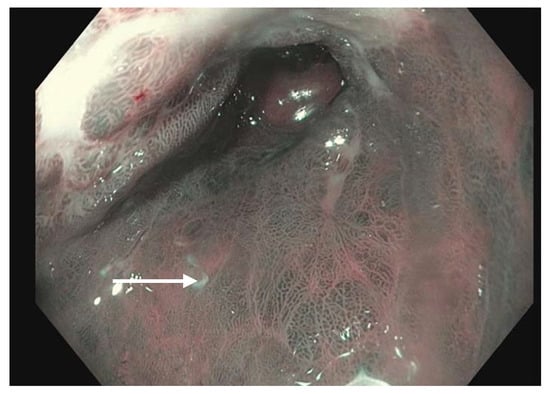

Barrett’s histology can be differentiated into non-dysplastic and dysplastic types; dysplastic Barrett’s esophagus can be further graded as low-grade dysplasia (LGD) or high-grade dysplasia (HGD). Many classification systems have been proposed with varying validity. Narrow band imaging (NBI) has been used to classify Barrett’s lesions by endoscopic appearance by their mucosal and/or vascular patterns. In this system, dysplasia is identified by irregular mucosa and vascularity, while intestinal metaplasia is identified by an endoscopic appearance of ridging or villous pattern [42]. The Japan Esophageal Society (JES) classifies endoscopic vascularity by mucosal and vascular shape, categorizing them into either regular or irregular. The JES system showed promising diagnostic accuracy and reproducibility [43].

Virtual chromoendoscopy uses technology built directly into the endoscope. The most widely used system is the Olympus narrow band imaging (NBI) (Figure 1) which applies a red–green–blue light filter to maximally highlight the surface mucosa and vascular pattern of the tissue being examined [46]. This narrower spectrum of 400–540 nm (compared to 400–700 nm white light) is matched to the absorption of hemoglobin, causing tissues such as blood vessels and blood to appear darker compared to the surrounding mucosa. Other widely used systems include the Fujinon Intelligent Color Enhancement (FICE) and the Pentax iScan which capture white light images and digitally process them to enhance the surface mucosa and vascular pattern [47]. A meta-analysis of nine studies showed a pooled sensitivity and specificity of greater than 94% each of detecting BE with NBI [48]. A separate study indicated an overall reduction in the number of biopsies while still detecting high-grade dysplasia (HGD) and early adenocarcinoma when white-light and NBI endoscopy were compared [49]. Virtual chromoendoscopy adds no cost, additional time or risk to the patient while providing a useful adjunct during routine endoscopy.

Narrow band imaging applied to a segment of Barrett’s esophagus (white arrow).